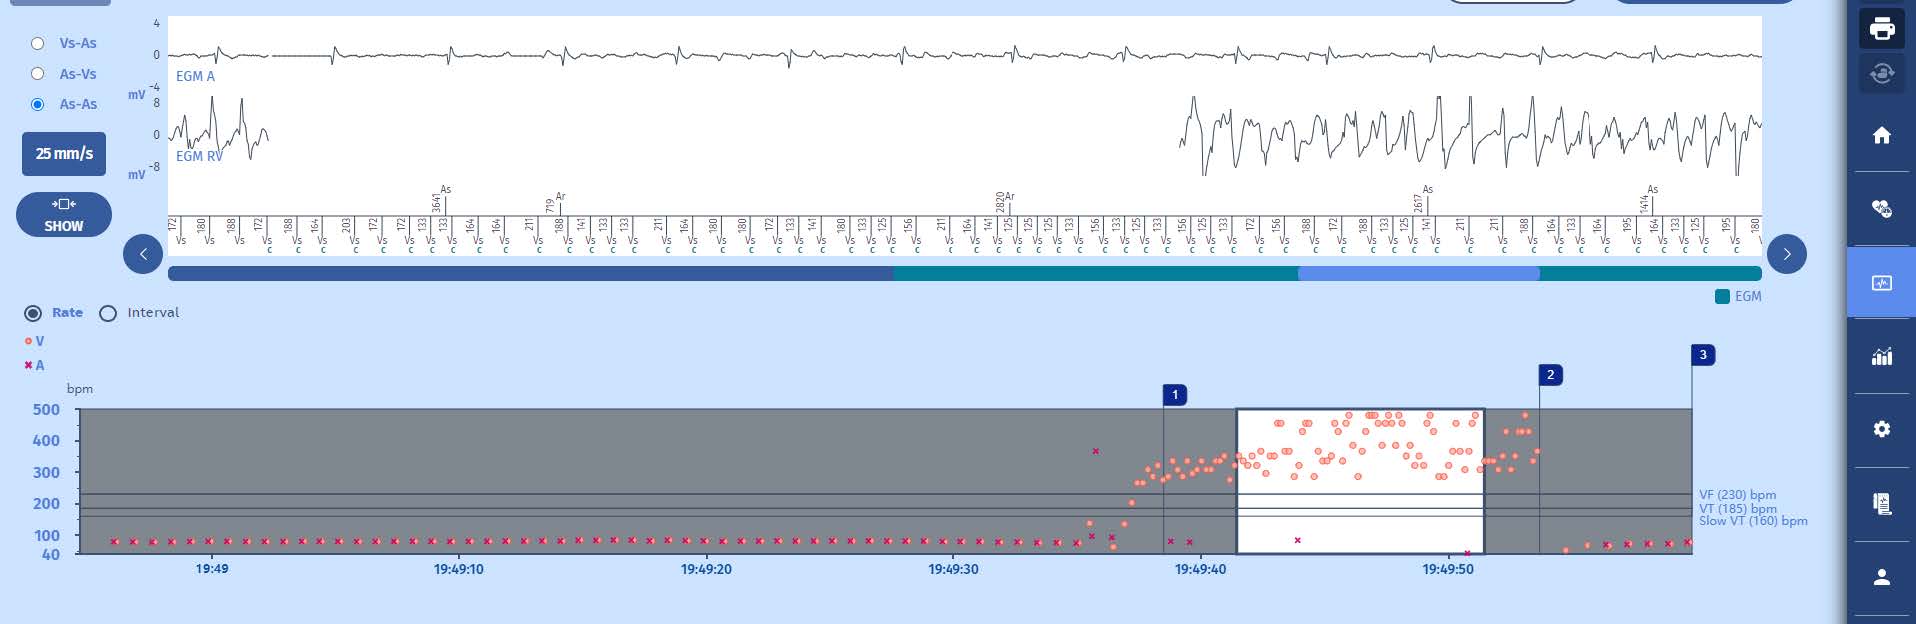

Here is the overview screen, notice that there has been one episode with therapies;

Tachogramme

Onset of a very fast tachycardia in the VF zone with high cycle variability, for which a quick diagnosis of VF is made with delivery of a shock restoring the slow rhythm.